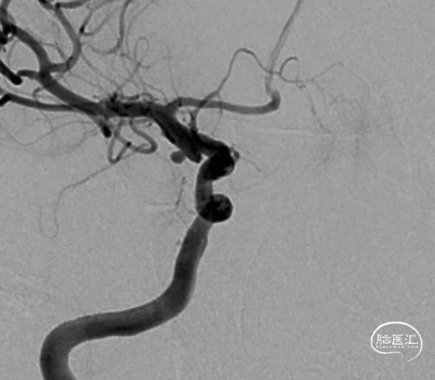

术前造影:后交通微小动脉瘤

后交通微小宽颈动脉瘤。

开颅风险较高,微小动脉瘤(宽颈),介入亦风险较高,又是颈内动脉(大流量高压力)后交通段动脉瘤,术中一旦破裂面临死亡的可能性较大。先预置支架导管,然后再置入动脉瘤内微导管,成蓝,必要时支架辅助栓塞动脉瘤。